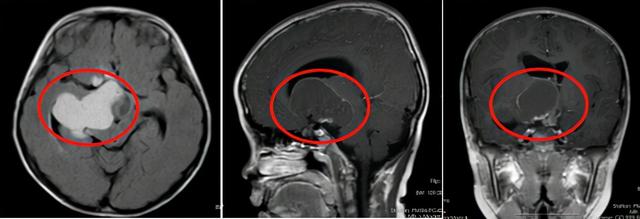

术前影像检查

我院影像学检查提示患儿鞍右侧有囊实性占位性病变。右心室梗阻性脑积水。神经内科主任穆林森仔细研究了患儿的影像学检查结果,初步怀疑是良性脑肿瘤。根据成像数据,病变大约有一个鸡蛋大小。穆林森建议早期手术切除。

经过多方讨论,神经内科九科团队为患儿实施手术,成功切除肿瘤约5.6cm4.4cm6.3cm,术后病理结果提示颅咽管瘤。